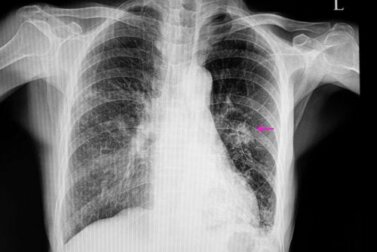

In diesen Fällen sind die Knoten in der Regel unregelmäßig auf dem Röntgenbild zu erkennen. Die Ränder sind nicht klar definiert. Außerdem sind sie meist kleiner als dies bei gutartigen Knoten der Fall ist. Oft liegen folgende Risikofaktoren vor:

Danach sind verschiedene bildgebende Untersuchungen nötig, um den Knoten genau zu lokalisieren. Damit kann man auch die genauen Eigenschaften feststellen: Die Form und Größe des Knotens sind wichtig, um zwischen einem gutartigen und einem möglicherweise bösartigen Knoten zu differenzieren.

In der Regel verwendet der Arzt eine Röntgenaufnahme des Thorax sowie eine Computertomographie zur Diagnose. Um die genaue Ursache für den Knoten in der Lunge festzustellen, ist zum Teil auch eine Biopsie nötig, um das Gewebe zu analysieren.